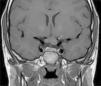

ONGs account for 85% of low-grade gliomas (pilocytic astrocytomas) in patients with NF1, and affect between 15% and 30% of children aged between 3 and 5 years.36,37 They are a diagnostic criterion for the disease. Most cases are asymptomatic, but they can cause loss of vision in up to 12% of patients37 or provoke early onset of puberty.35 In view of the high incidence of ONGs, close ophthalmological follow-up is advisable in children with NF1, whether this is clinical or radiological, as clinical detection by physical examination can be difficult and some neuropediatricians prefer conducting complementary tests (Fig. 6).37 The remaining 15% of low-grade gliomas also occur more frequently in the first 10 years of life, and can appear in any part of the brain. They are manifest clinically as headaches, unstable gait, or lethargy.35 By contrast, high-grade gliomas (glioblastoma multiforme) are more often seen in young adults. The risk of such tumors is 5-fold greater in patients with NF1 than in the general population and prognosis is poor.35,38 Treatment for ONG in patients with NF1 is usually conservative, unless a decrease in visual acuity or progression in the size of the tumor in imaging tests is observed. If necessary, first-line treatment is chemotherapy with vincristine and carboplatin. Radiotherapy is not recommended given the high risk of secondary tumors. Surgery is reserved for large orbital tumors in which the patient has no useful vision, when the cornea is exposed, or if there is proptosis.39